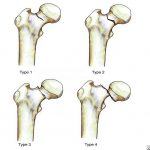

Chấn Thương Xương Đùi | Bài giảng CĐHA *

Gãy xương đùi là một chấn thương phổ biến, đặc biệt là ở những người lớn tuổi. Gãy xương đùi ở người cao tuổi thường gây ra bởi té ngã tưởng như không nguy hiểm. Ở những bệnh nhân trẻ tuổi nguyên nhân thường gặp hơn của một chấn thương thường là do va đập mạnh như tai nạn xe hơi. Gãy xương đùi cũng có thể được gây ra bởi xương bị suy yếu từ khối u hoặc nhiễm trùng, hay còn gọi là gãy xương bệnh lý…